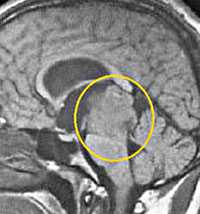

Диагностика: МРТ с контрастным усилением — стандартное исследование при опухолях этой локализации. При пинеоцитоме обнаруживают небольших размеров округлое образование в пинеальной области, с чёткими границами, активно и гомогенно накапливающее контраст и вызывающее компрессию пластинки четверохолмия. Для пинеобластомы характерны все признаки злокачественной быстро прогрессирующей опухоли (инфильтративный характер роста, гетерогенный сигнал с признаками некроза и кровоизлияний, большие размеры, субарахноидальные метастазы).

Пинеоцитома. МРТ в режиме Т2 и Т1 выявляется солидного строения опухоль задних отделов III желудочка мозга. На фоне в/в контрастирования определяется выраженный и достаточно гомогенный характер контрастирования опухоли.